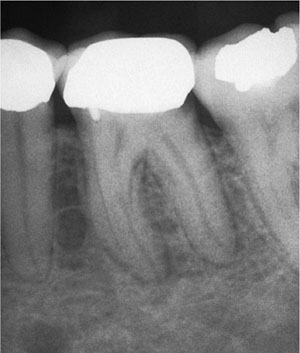

Once the diagnosis has been confirmed, it is essential that the prognosis of the tooth is determined. Restorability must first be established, taking into account both the quantity, quality and location of coronal tissue, and the periodontal status. Carefully “walking” a periodontal probe around the gingival margin of the tooth will highlight the presence of significant features such as vertical fractures, which may have a serious impact on restorability and treatment planning. It is common for teeth that require endodontic treatment to be heavily restored or broken down and infected. Caries must be removed to prevent leakage and minimise the risk of microbe-laden carious dentine entering the root canal space during treatment (Fig 1-1).

Fig 1-1 Radiographic signs of caries at the distal margin of a lower molar crown. The crown must be removed to fully excavate caries and assess restorability before root canal treatment can commence.